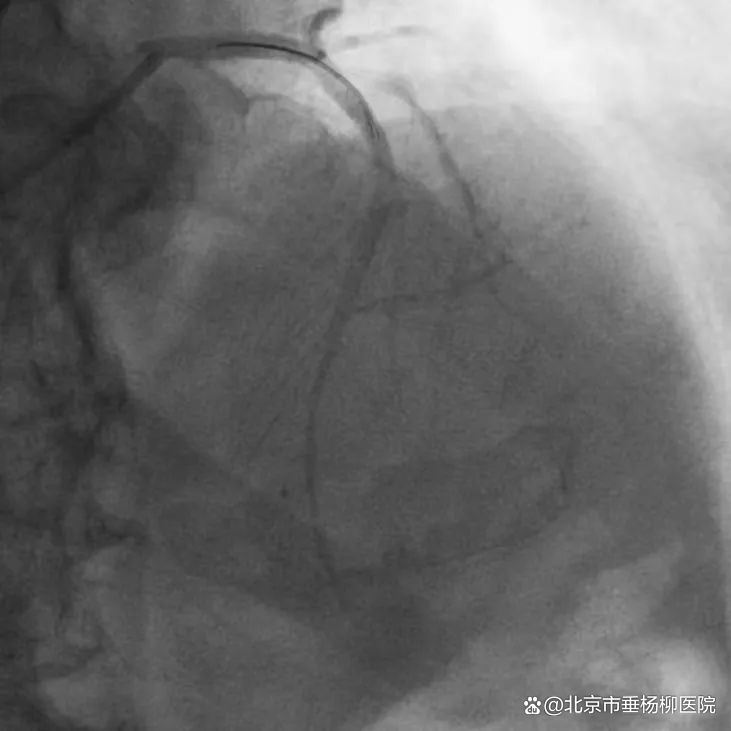

心内科主任医师包恩泽面对挑战,迎难而上,在主动脉球囊反搏(IABP)循环支持及在大量血管活性药物维持生命体征下,指引导管到位、导丝顺利通过病变到达血管远段,球囊扩张,支架植入。从患者到达医院急诊至IABP置入、血管开通,仅用73分钟。患者左主干至前降支顺利植入2枚支架,胸痛明显减轻,生命体征逐渐平稳。

▲支架植入后